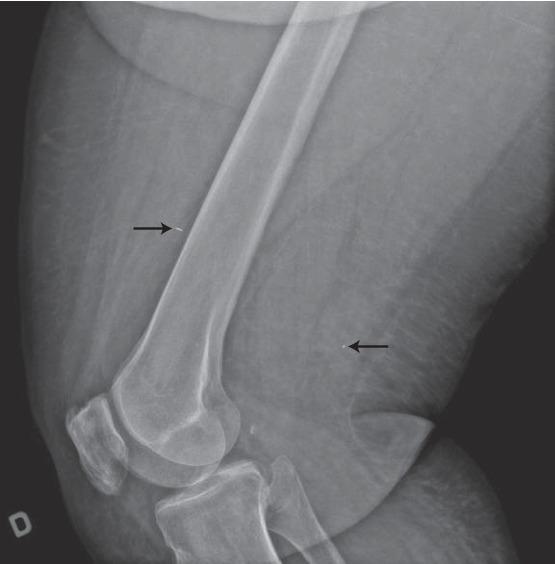

默克尔细胞癌是一种进展迅速的非黑色素瘤皮肤癌,复发风险高。当复发发生时,其预后较差,且缺乏针对此类病例的管理指南。本文描述了一个具有挑战性的病例,其中创新性地使用碘 - 125放射性粒子使我们能够精确识别并切除两个不可触及的复发性结节。由于过去两次切除和两个疗程的放疗后存在瘢痕组织,手术的安全性和准确性受到了影响。放射性粒子定位在乳腺癌中是一种广为人知的操作,显示出在其他癌症类型和复杂临床情况中扩展应用的潜力。

https://cdn.ncbi.nlm.nih.gov/pmc/blobs/9d98/7321529/80d6ca0b1076/CRIS2020-1789185.003.jpg

https://cdn.ncbi.nlm.nih.gov/pmc/blobs/9d98/7321529/930949cba570/CRIS2020-1789185.001.jpg

https://cdn.ncbi.nlm.nih.gov/pmc/blobs/9d98/7321529/e339b5685cc1/CRIS2020-1789185.002.jpg